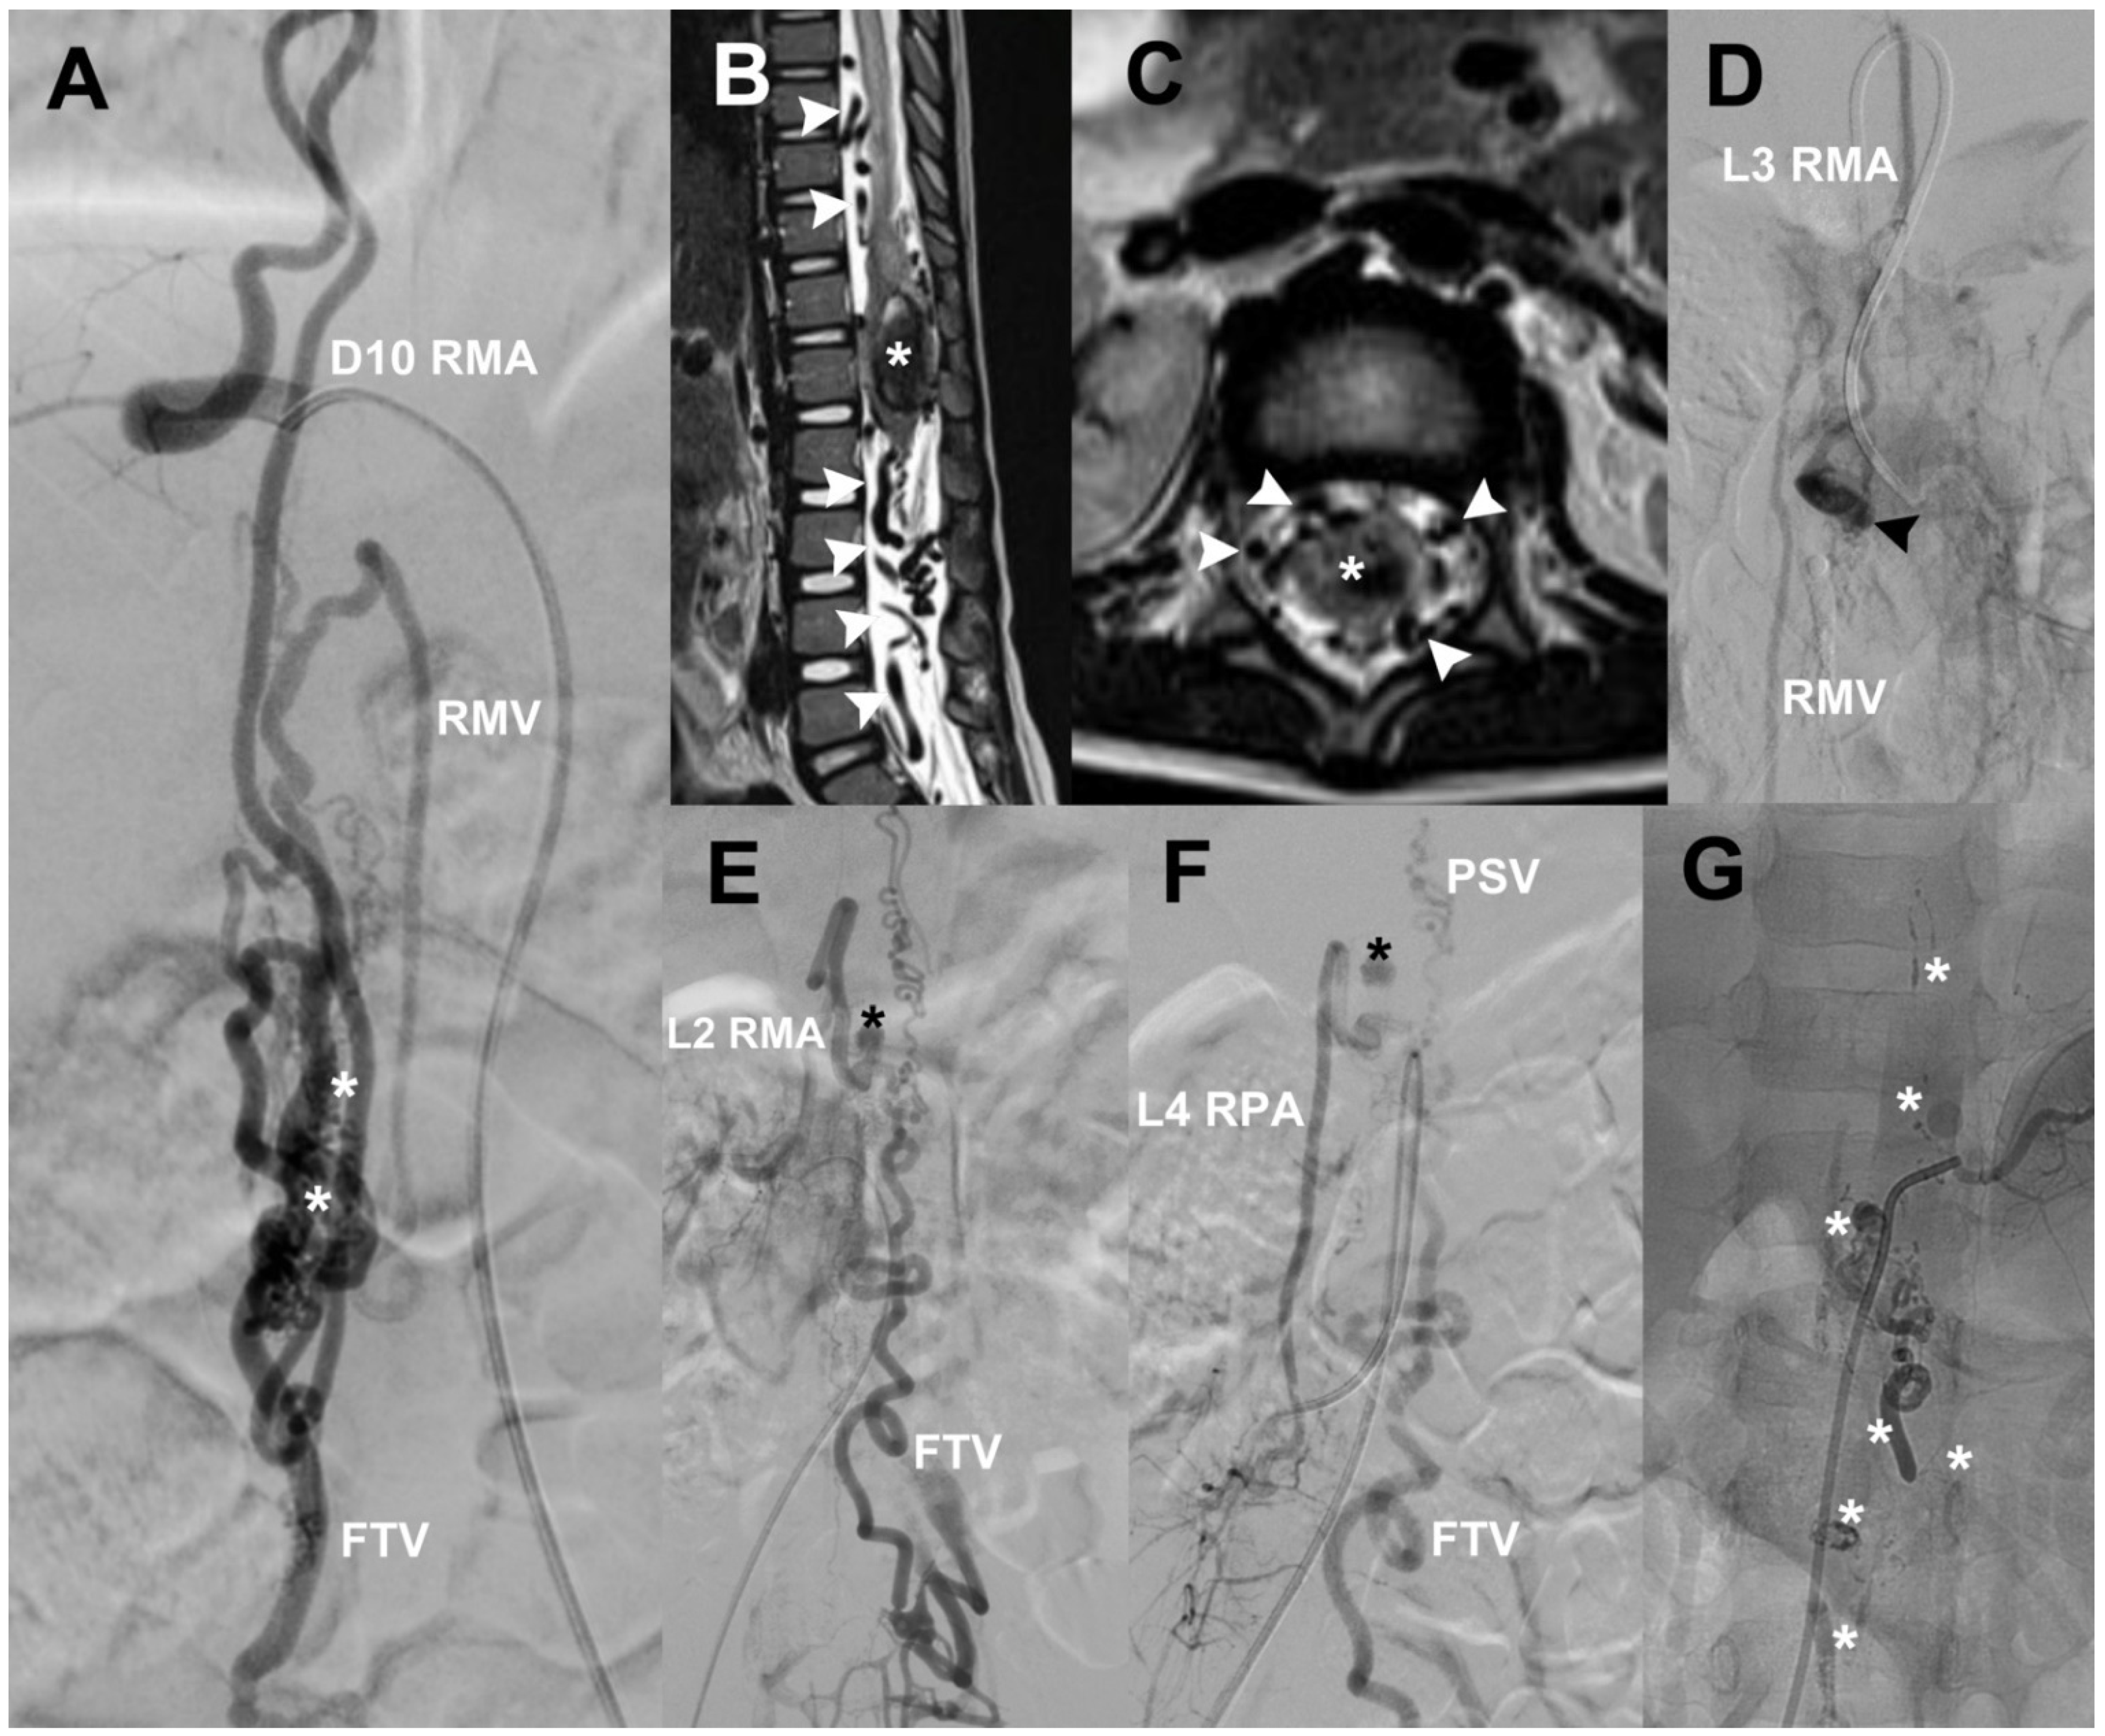

A 5-year-old male with suspicion of Cobb syndrome developed sudden paraplegia, pain in both legs, and sphincter incontinence. MRI showed void signals around the CM and hematomyelia. sDSA was made and showed a diffuse and fistulous sAVM at CM, with afferents from right D10, L2 RMA, left L3 RMA, and L4 RPA with a diffuse nidus at L1–L3, and venous drainage towards RMV, FTV, and PSV. We found an arterial aneurysm at L2 and a venous aneurysm at L3 (Figure 5). First, the right D10 artery was catheterized and then embolized with Histoacryl, resulting in complete occlusion of the nidus. Because of hematomyelia, the patient was operated on for partial resection of the sAVM, evacuation of hematoma, and laminoplasty. Seven months later, he was submitted to embolization through left L3 RMA, right L2 RMA, and right L4 RPA. After the procedure, we achieved complete occlusion of the lesion; at that time, the patient’s neurological status improved to paraparesis 4/5. The 6-month and 1-year control sDSA did not show any vascular lesions.

Figure 5.

(A) A diffuse CM sAVM case; white asterisks mark the place of the diffuse nidus, and the first afferent is right D12 RMA while the drainage goes to RMV and FTV. Lumbosacral T2-MRI shows flow voids (white arrowheads) and hematomyelia (white asterisks) (B,C). (D) One fistulous component at left L3 RMA; a venous aneurysm (black arrowhead) and its drainage through RMV. Other fistulas are seen at right L2 RMA (E) and right L4 RPA (F) while their drainage goes through PSV and FTV; a small arterial aneurysm (black asterisk) can be seen. (G) A negative control sDSA after Histoacryl embolization (white asterisks) and surgical management. CM = conus medullaris, RMA = radiculomedullary artery, RPA = radiculopial artery, RMV = radiculomedullary vein, FTV = filum terminale vein, PSV = posterior spinal vein.